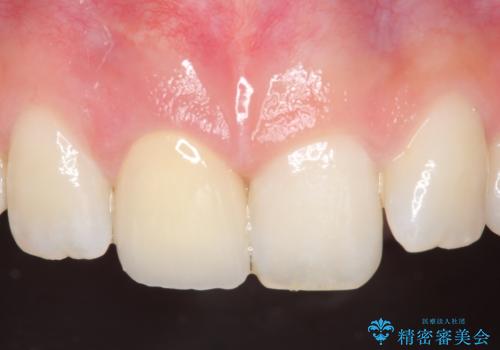

オールセラミッククラウン 痛みの引かない歯の治療

- 他院にて根管治療を行っていたが、痛みが引かないので診て欲しいといらっしゃった方の症例です。

マイクロスコープ下でラバーダムを使用しながら根管治療を行い、痛みが治まった後にオールセラミッククラウンによる補綴を行いました。

今回用いたオールセラミッククラウンはジルコニアフレームという白い素材の上にセラミックを盛っているため、審美性が非常に高いのが特徴です。